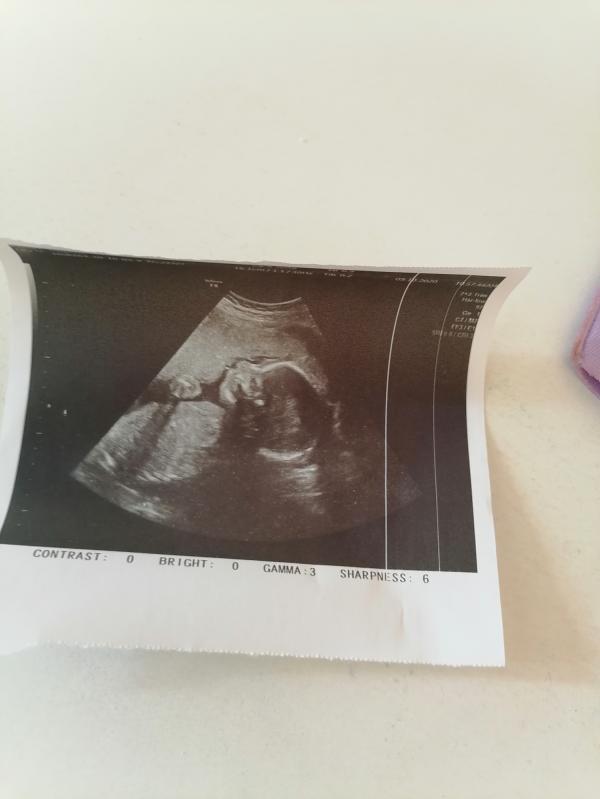

Какое же это счастье слышать с твоим малышом всё хорошо, видеть это крошечку, чувствовать его движения! В жизни правда всё такая мелочь по сравнению с этим... Наши детки нам достаются с трудом, кому то с муками, но оно того стоит... Мой мальчик начал быстро расти, я всё чётче и чётче чувствую его пиночки... Мой котёночек